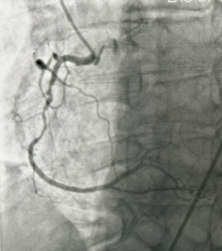

- During the procedure, a thin flexible tube (catheter) is inserted through an artery in the wrist or groin and guided to the heart. A colorless contrast dye is injected, allowing detailed X-ray images to show whether any coronary arteries are narrowed or blocked, and the exact location and severity of the blockage.

Angiogram showing detailed images of the coronary arteries and areas of narrowing.